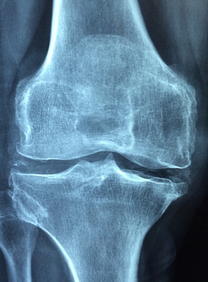

무릎 연골은 무릎 관절의 움직임을 도와주는 부드러운 조직입니다. 무릎 연골은 무릎 관절에서 마찰과 충격을 완화하여 뼈와 뼈가 부드럽게 움직일 수 있도록 도와줍니다. 무릎 연골은 건강한 상태에서는 매끄럽고 탄력적이며, 충격을 흡수할 수 있습니다. 하지만 연령과 함께 연골은 마모되며, 외상이나 질병으로 인해 손상을 입을 수도 있습니다. 무릎 연골손상은 무릎 통증, 불편감, 굴곡 제한 등을 유발할 수 있으며, 중증의 경우 수술이 필요할 수 있습니다. 따라서, 건강한 식습관과 적절한 운동, 적절한 보호장비 사용 등으로 무릎 연골 건강을 유지하는 것이 중요합니다.